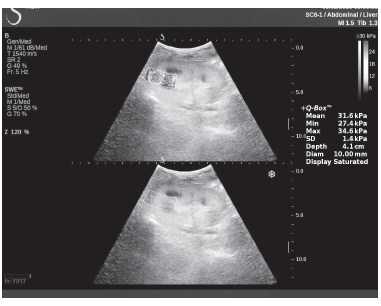

Клинический пример из первой группы. Пациент М., с хронической почечной недостаточностью. Трансплантация почки произведена от живого родственного донора. Трансплантат находится в правой подвздошной области. При нормальном функциональном состоянии трансплантата, показатели цветовой и спектральной допплерографии оценивались как удовлетворительные, с индексом резистентности не более 0,60 (рис. 1); показатели жесткости паренхимы почечного трансплантата при УЭСВ на различных участках составили от 20,05 до 29,18 кПа (рис. 2-4).

Рисунок 4. Исследование в режиме ультразвуковой эластографии сдвиговой волны у пациента М.: жесткость паренхимы в зоне нижнего полюса почечного трансплантата 16,8 кПа

Клинический пример из второй группы. Пациент К. перенес операцию пересадки почки от живого родственного донора. Трансплантат в левой подвздошной области. Индекс резистентности в междольковых артериях составил 0,70 (рис. 5). В сегментарных артериях индекс резистентности составил 0,66 (рис. 6). Показатели жесткости паренхимы почечного трансплантата при режиме УЭСВ составили от 31,6 до 36,9 кПа (рис. 7-9).

Рисунок 9. Исследование в режиме ультразвуковой эластографии сдвиговой волны у пациента К.: жесткость паренхимы у верхнего полюса почечного трансплантата 31,6 кПа

При снижении скорости кровотока и повышении индекса резистентности до 0,70 и более, как в первой, так и во второй группах, показатели УЭСВ составили от 28,00 до 39,45 кПа. Повышение жесткости паренхимы почечного трансплантата, на наш взгляд, связано с начавшимися изменениями (фиброза) в паренхиме почки. При повышении индекса резистентности более 0,70 показатели жесткости паренхимы при УЭСВ является дополнительным критерием, позволяющим оценить функциональное состояние почечного трансплантата. Ультразвуковая эластография ― новая развивающаяся методика, чувствительность, специфичность и точность которой увеличиваются при комплексном использовании с другими методами исследования. Анализ результатов проведенных исследований выявил значительные клинические возможности и перспективы применения метода ультразвуковой эластографии сдвиговой волны в оценке состояния почечного трансплантата. Полученные данные о диагностической точности метода позволяют использовать результаты в целях принятия решения о дальнейшем ведении пациента и тактике лечения [4].